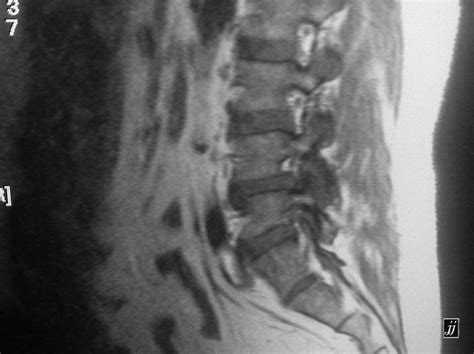

• Imaging Tests: X-rays are the baseline, but an ultrasound or MRI is far more effective at detecting a small joint effusion because these methods can visualize soft tissues and identify fluid pockets that X-rays might miss.

When you visit a doctor for joint swelling, they will typically follow a diagnostic process to uncover the root cause. This often begins with a physical examination to check for localized tenderness and the presence of fluid. To get a clearer picture, they may utilize several tools: